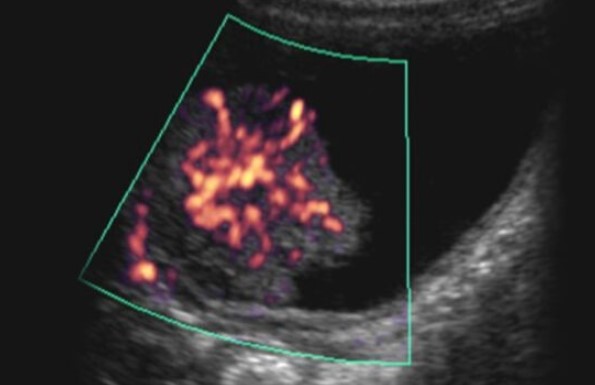

A physical examination that includes a bimanual examination assists in the diagnosis. Other diagnostic measures include: cystography; urinary cytology studies; cystoscopy; computed tomography (CT) scan; magnetic resonance imaging (MRI); abdominal ultrasound; and intravenous (IV) urography. For tests related to organs specific to women, see Diagnostic Code: 7628 Benign neoplasms of the gynecological system or breast.